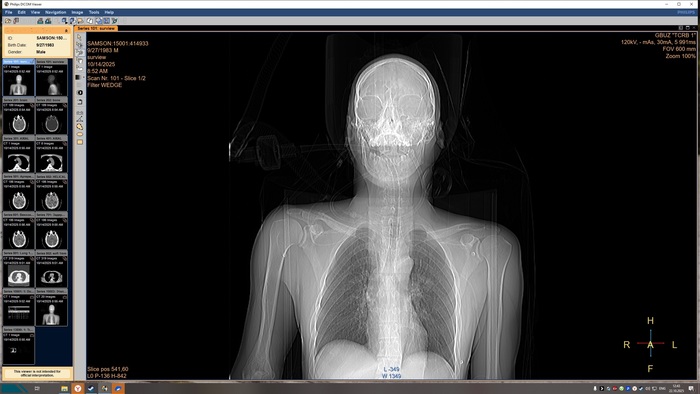

Описание КТ прикрепляю, а снимки будут в конце поста, по-другому у меня не получилось.

Снимки КТ